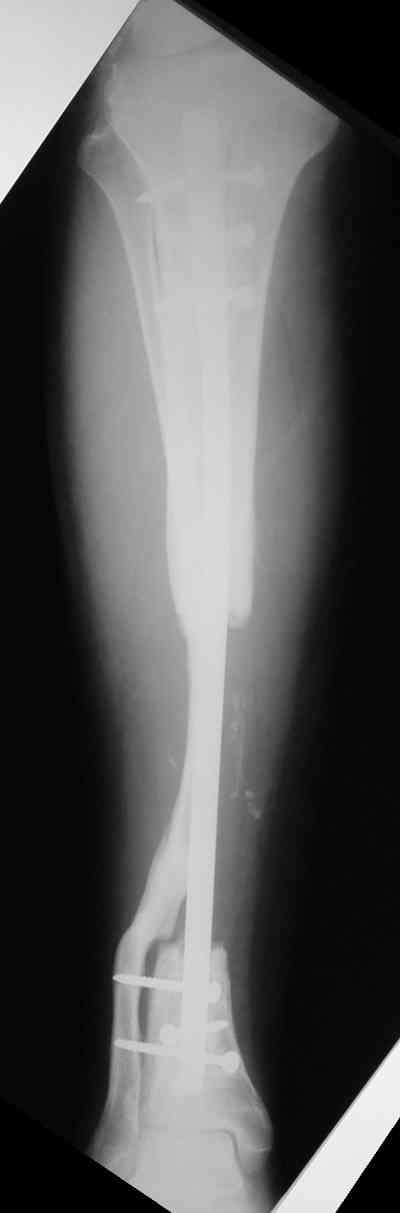

Владимир, свободная костная пластика на фоне свища вряд ли оправдана. Почему не рассматриваете вариант транспорта кости по Илизарову? Что собираетесь делать с латентной инфекцией? Одни антибиотики не помогут, необходима полноценная хирургическая обработка, Мы бы подумали о цементном спейсере с антибиотиками, бусах. После купирования инфекции переходить к замещению

дефекта: за счет удлинения концов б\б кости или тибиализации м\б. На начальном этапе фиксация только в аппарате, в последствие для удержания достигнутого можно перейти на фиксацию интрамедуллярным штифтом (см. вложенные файлы)